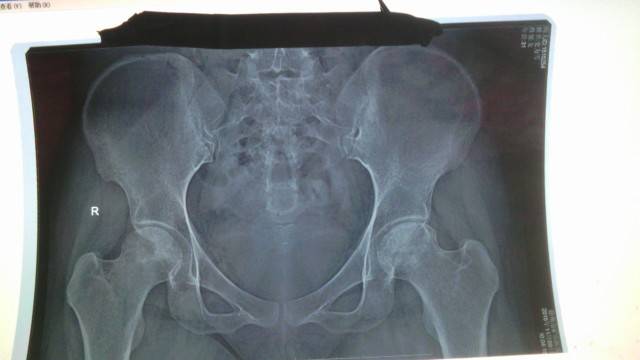

看片子没大有区别,不继续发展就是好的,不过,我是第二年就不太疼了,也是吃了中药,泡脚,加上TDP灯理疗等这些,现在不走时间长是不会疼,出门骑车买个菜,做个公交还可以